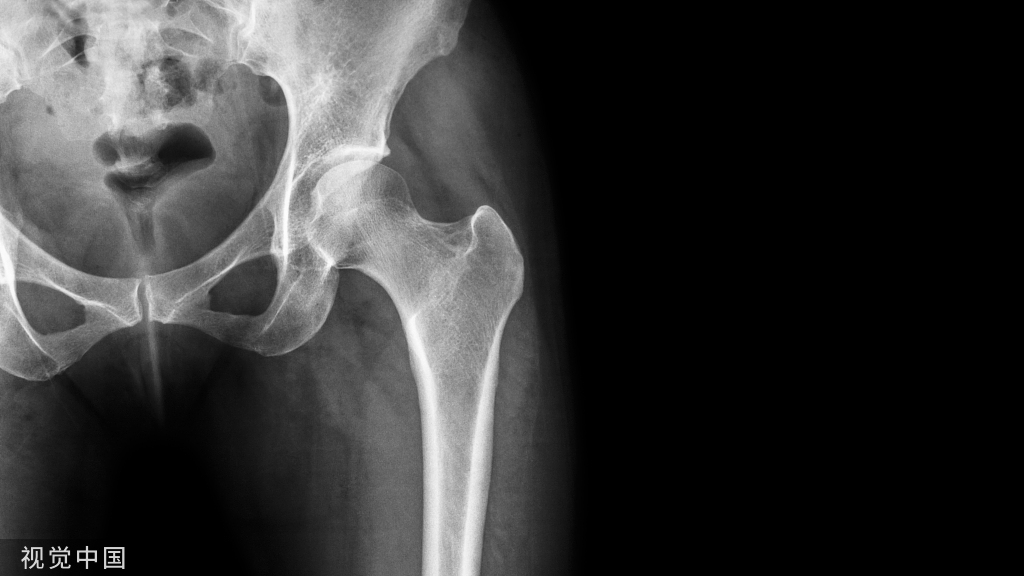

9、胫腓骨骨折

整复前根据病人伤后软组织情况,结合X线片明确骨折类型、部位,移位程度,确定整复步骤(图5-34)。移位较多,肌肉强者,可用腰麻;移位小者亦可用神经阻滞或局麻。